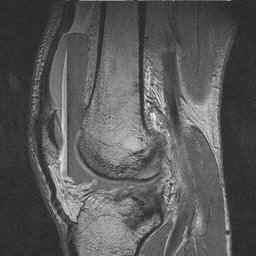

This gradient echo sagittal sequence demonstrates a lipohemarthrosis of the knee with four distinct layers. Gradient echo sequences are most sensitive to local field inhomogeneties and the artifact from chemical misregistration is readily apparent here.

The FBI Sign: CT, MRI, and Radiographic Appearance of Lipohemarthrosis